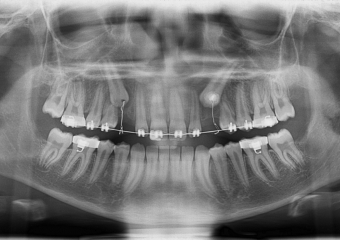

Rx Panorâmico - Caninos respondendo ao tracionamento - Clínica Cliniface

Rx Panorâmico - Caninos respondendo ao tracionamento